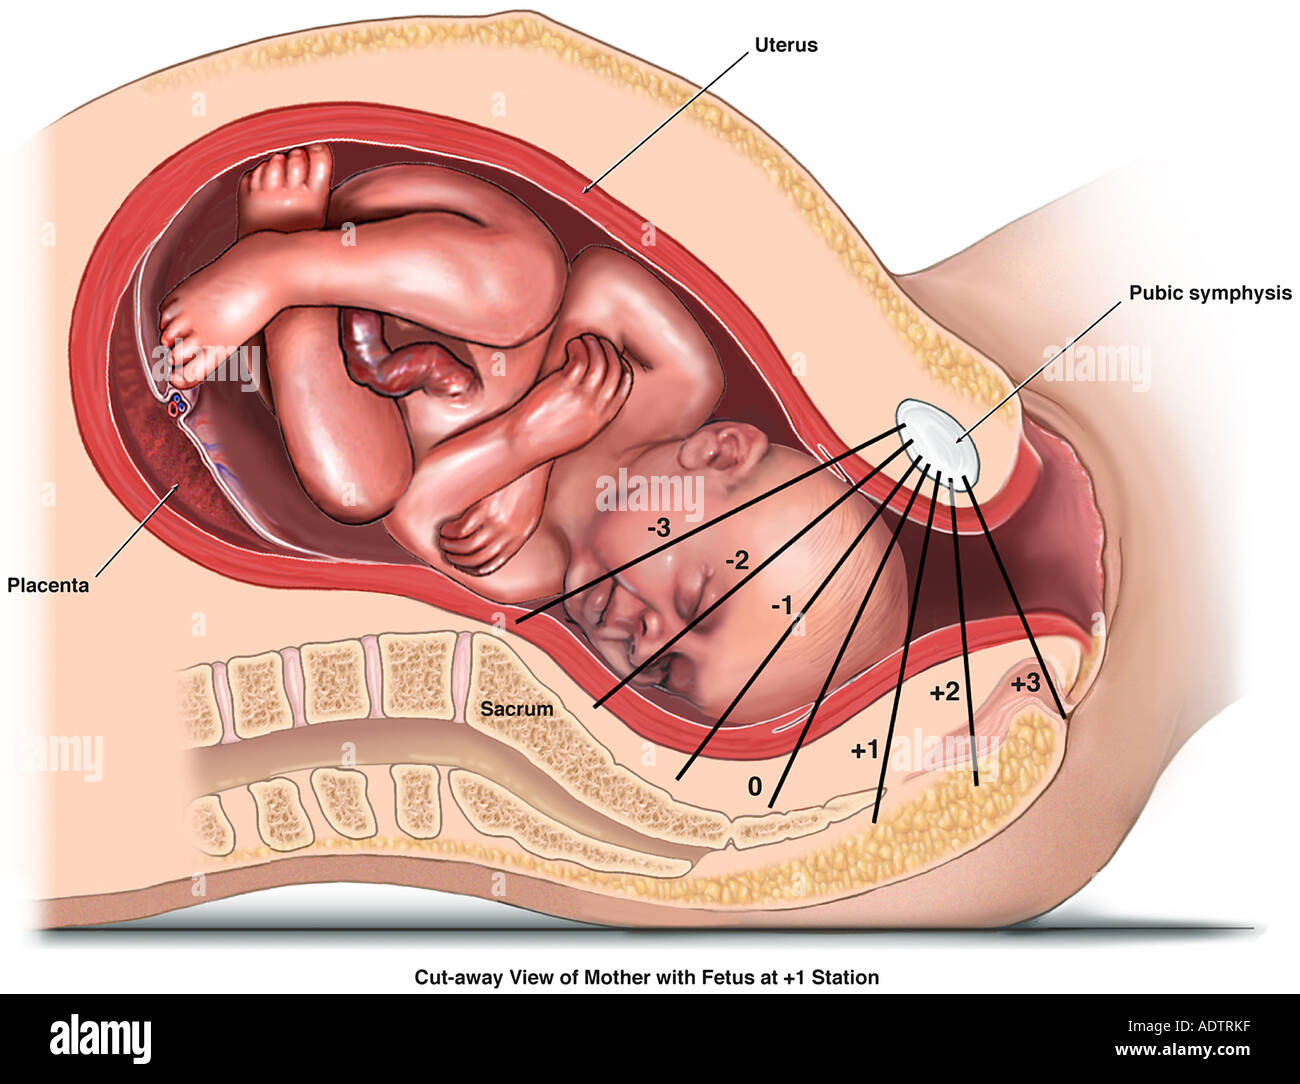

Расположениребенка в матке

Расположение ребенка в матке